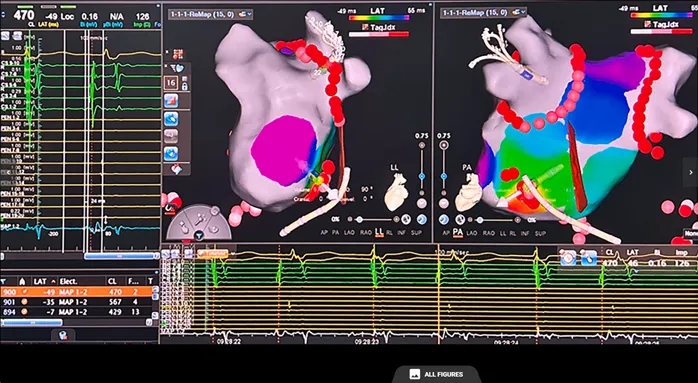

肺静脉隔离术后,患者自发出现频繁房性早搏,呈二联律及阵发性窄QRS波心动过速。二联律房早的起源点标测显示最早激动位于冠状窦远端及其对应心内膜区域(图4)。

图4 二联律房性早搏的标测(最早激动点位于冠状窦远端)

随后,术者团队采用多电极标测导管,在心动过速短暂稳定发作期间进行标测,每次专注于一种形态。共识别出两种主要房性心动过速形态:

1)房速1:心动过速周长450ms,呈向心性冠状窦激动顺序。右房标测显示最早激动点位于希氏束附近;经房间隔穿刺后行左房标测确定最早激动点位于二尖瓣峡部上方(约11点钟方向)(图7)。

2)房速2:亦呈向心性冠状窦激动顺序,但发作持续时间较短。初步标测提示右房激动早于左房(左房最早激动点疑似在Bachmann束插入处附近)(图8)。随后精细标测右房,将最早激动点定位于界嵴下部(图9)。

图7 房速1的标测(最早激动点位于二尖瓣环高位)

图8 房速2的标测(右房优先激动)

图注:左房最早激动点疑似位于Bachmann束插入处附近

图9 房速2的标测

图注:右房最早激动点位于界嵴下部